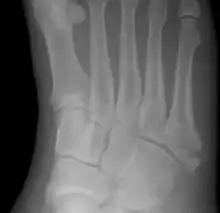

| Jones fracture as seen on Xray | |

The fracture typically occurs when the toes are pointed and the foot bends inwards.[6][2] This movement may occur when changing direction while the heel is off the ground such in dancing, tennis, or basketball.[9][10] Diagnosis is generally suspected based on symptoms and confirmed with X-rays.[3]

Diagnostic X-rays include anteroposterior, oblique, and lateral views and should be made with the foot in full flexion.